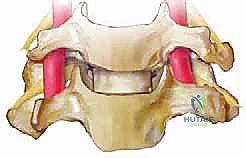

التشريح الدقيق للعمود الفقري العنقي لفهم العملية

لفهم أهمية عملية ACDF، يجب أولاً فهم تشريح الرقبة. يتكون العمود الفقري العنقي من سبع فقرات عظمية (C1 إلى C7). بين كل فقرة وأخرى (باستثناء الأولى والثانية) يوجد "قرص فقري" (Disc) يعمل كوسادة لامتصاص الصدمات وتسهيل حركة الرقبة.

يتكون هذا القرص من جزأين رئيسيين:

1. الحلقة الليفية (Annulus Fibrosus): الغلاف الخارجي القوي والمرن.

2. النواة اللبية (Nucleus Pulposus): مادة هلامية ناعمة في المركز.

خلف هذه الأقراص والفقرات، يمر الحبل الشوكي داخل القناة الشوكية، وتتفرع منه الأعصاب الشوكية التي تخرج عبر فتحات صغيرة (الثقوب الفقرية) لتغذي الكتفين، الذراعين، واليدين. أي خلل في هذا النظام الدقيق يؤدي إلى كارثة عصبية.